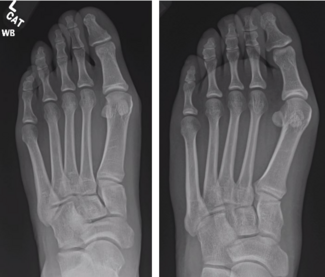

Since its introduction, minimally invasive surgery (MIS) for bunions has seen advancements in technique that have benefitted patients. Drawing on their experience and technical modifications, these authors offer step-by-step pearls for...